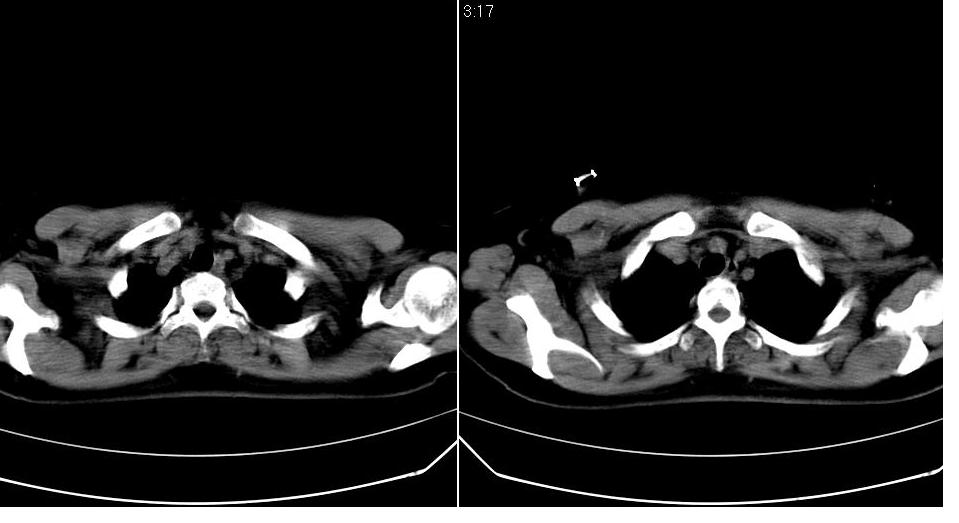

女 40岁,胸片体检发现右肺肿块,无任何症状。

下叶背段多发性小腺泡结节,考虑结核。

考虑右肺下叶背段继发性肺结核。